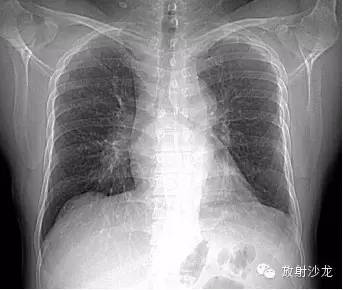

第一例:

44岁女性,因左乳腺结节行胸部CT检查发现胸部病变。

三幅图为典型的胸部结节病表现,肺门纵隔多发淋巴结肿大,各淋巴结不融合、不坏死、不侵犯邻近结构。右侧气管旁、右侧肺门、左侧肺门、主肺动脉窗淋巴结肿大,为1,2,3,4淋巴结。

双肺底见间质性病变。

CT拟诊结节病,呼吸内科建议定期观察。未经任何治疗11个月后复查示肺门纵隔淋巴结正常,双肺底间质性病变消失。左乳腺结节无变化(图略)